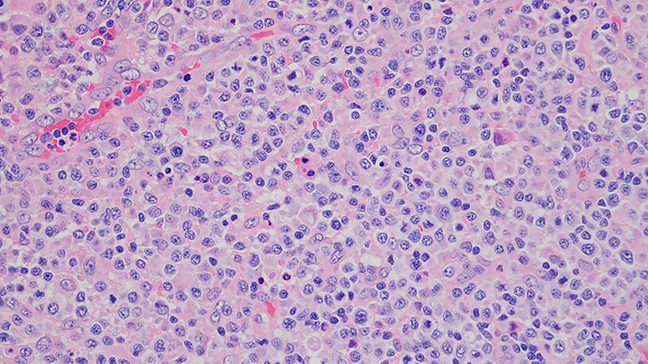

View Clinical TrialsLymphoma is a general term for cancers that develop in the lymphatic system, which is part of the body’s immune system. Non-Hodgkin lymphoma can start from multiple types of lymphocytes (a kind of white blood cell), including B and T lymphocytes.

Lymphoma is a general term for cancers that develop in the lymphatic system, which is part of the body’s immune system. Non-Hodgkin lymphoma can start from multiple types of lymphocytes (a kind of white blood cell), including B and T lymphocytes.

They may start in the bone marrow, spleen, thymus or lymph nodes and spread to other parts of the body.